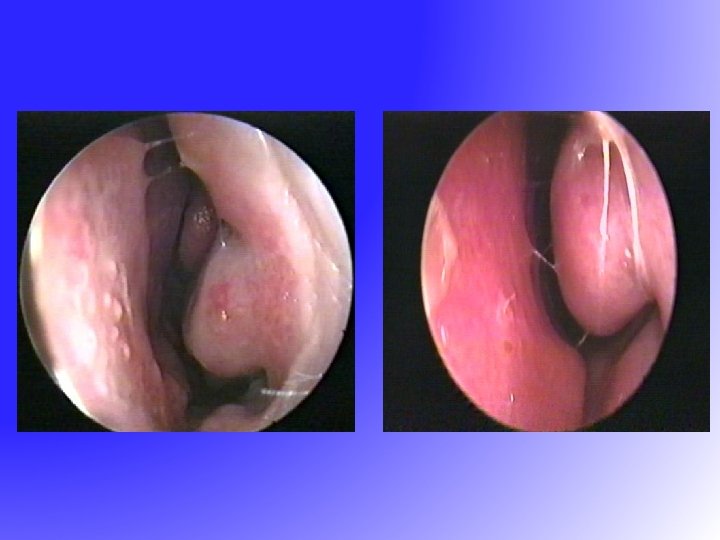

Diagnosis – Present illness, past medical history, family history, environmental history and impact on quality of life. Lungs and Skin – Nose, Eyes, Ears, – edematous Inferior turbinate, polyps

Diagnosis – Present illness, past medical history, family history, environmental history and impact on quality of life. Lungs and Skin – Nose, Eyes, Ears, – edematous Inferior turbinate, polyps

Post FESS

Post FESS